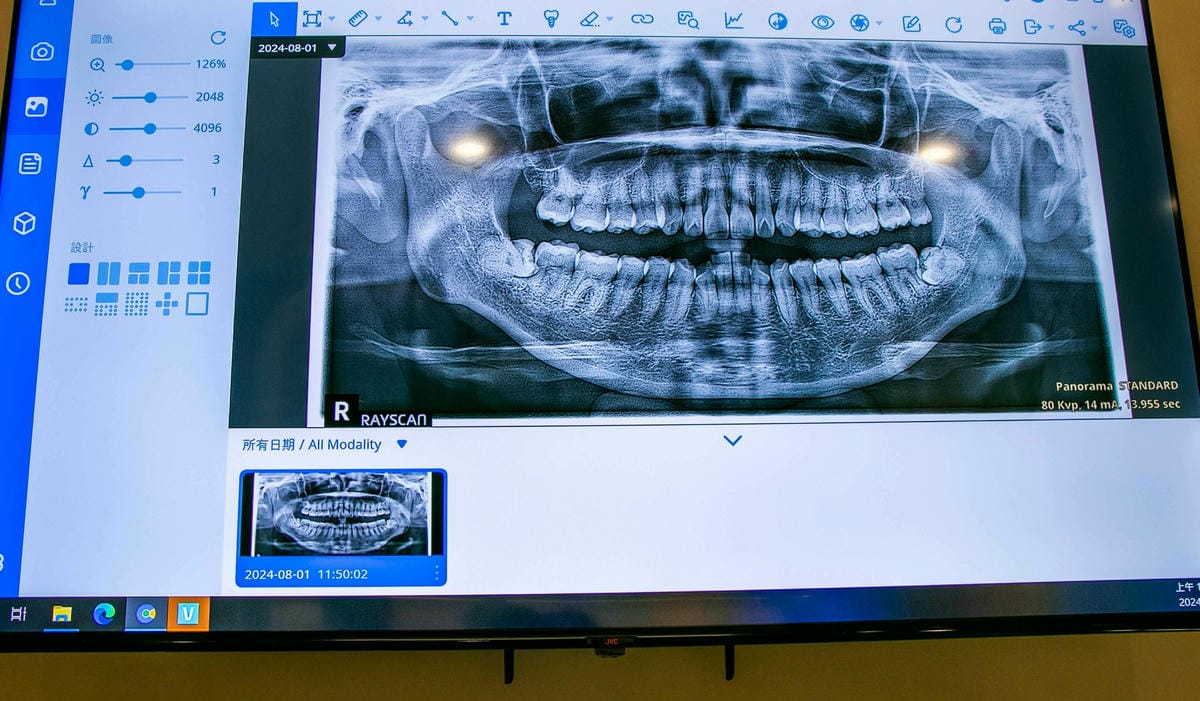

來到二樓,因為要等著照全口牙掃描X光攝影,這樣才知道怎麼樣矯正,

來做全口掃描X光攝影,如果要找全口重建、牙齒矯正的朋友,

務必要找像這樣有先進設備的牙醫診所,這樣才能準確把人工植牙放在哪個位置掌握住。